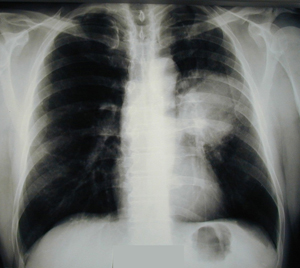

Εικόνα 1

Ακτινογραφία θώρακος ( οπισθιο-πρόσθια ) που δείχνει ευμεγέθη όγκο της αριστερής πύλης.